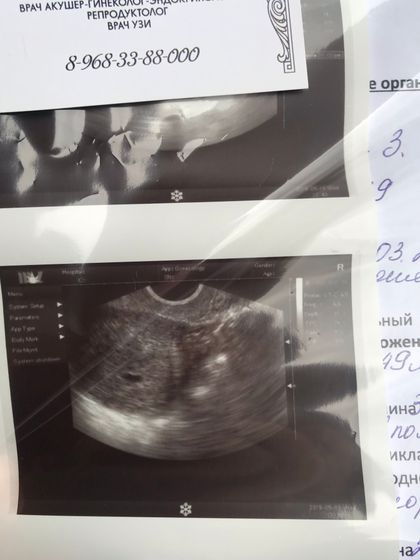

Ура! Моя крошка в матке, развиваемся по сроку, отчетливого сердцебиения нет, но врач говорит, что видит эту пульсацию!

Срок 5-6 недель.

Глянула, 10,9 мм